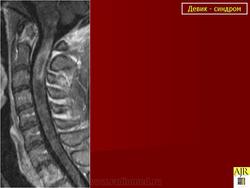

В диагностике БД помимо оценки клинической картины существенное значение имеют исследования ЦСЖ и проведение МРТ спинного мозга. ЦСЖ в острой фазе заболевания характеризуется появлением незначительного (50 клеток/мм3) лимфоцитарного плеоцитоза. Характерные для РС олигоклональные антитела могут обнаруживаться только у 20 % больных с БД [21]. Характерный МРТпризнак БД - выявление в Т2Wрежиме гиперинтенсивного очага (очагов) поражения как серого, так и белого вещества спинного мозга, вытянутого в краниокаудальном направлении, протяженностью не менее трех сегментов (рис. 3). Эти очаги способны к накоплению контраста, редко имеет место массэффект. Диагностическую значимость имеет отсутствие характерных для РС очагов при одновременном проведении МРТ головного мозга [4].

Данные МРТ и аутопсии свидетельствуют о возможности образования бляшек не только в спинном мозге и зрительных нервах, но и в перивентрикулярном белом веществе, редко - в стволе мозга и мозжечке. По данным МРТ, поражения спинного мозга носят больше некротический характер и затрагивают не менее трех сегментов.

Основные МРТ-проявления оптикомиелита характеризуются:

•тяжелым поражением спинного мозга с наличием очагов, занимающих по протяженности несколько сегментов

•по поперечнику часто наблюдается тотальное или субтотальное поражение

Для острого периода миелита характерно веретенообразное утолщение спинного мозга в зоне воспаления, а в отдаленном периоде - выраженная его атрофия. При рассеянном склерозе очаги в спинном мозге по длиннику редко захватывают зону более одного сегмента, а на поперечных срезах характерно асимметричное парциальное поражение. Оптикомиелит также характеризуется последовательным или одновременным двусторонним тяжелым поражением зрительных нервов, с отеком в остром периоде и атрофией впоследствии. Изменения в зрительных нервах видны как при исследовании глазного дна, так и на МРТ. Последние, в отличие от рассеянного склероза, захватывают зрительные нервы на большом протяжении. В головном мозге регистрируются единичные мелкие очажки, не имеющие специфических признаков. В некоторых случаях имеет место более массивное поражение головного мозга, соответствующее рассеянному склерозу.